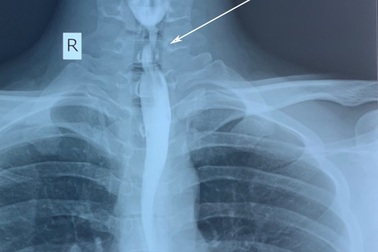

Bỏng thực quản vì uống nhầm chất tẩy rửaSau khi uống nhầm chất tẩy rửa, nam thanh niên bị bỏng thực quản và gây sẹo làm hẹp dần lòng thực quản dẫn đến khó nuốt thức ăn.